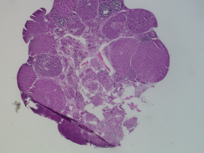

Genus: Mus (mice)

Species: Mus musculus ()

Donor ID: SX_MM_Control_1

Life Stage: prepubertal

Age: 0 years, 25 days

Accession #: MDB0000578

Ovary position: unspecified

Location: wholeOvary

Section thickness: 5 microns

Fixation: neutralBufferedFormalin10

Stain: Hematoxylin and Eosin

Immunohistochemistry: None

Experimental treatment: Control - mock treatment - PBS, IP injection, 5 days

Other pathology: None